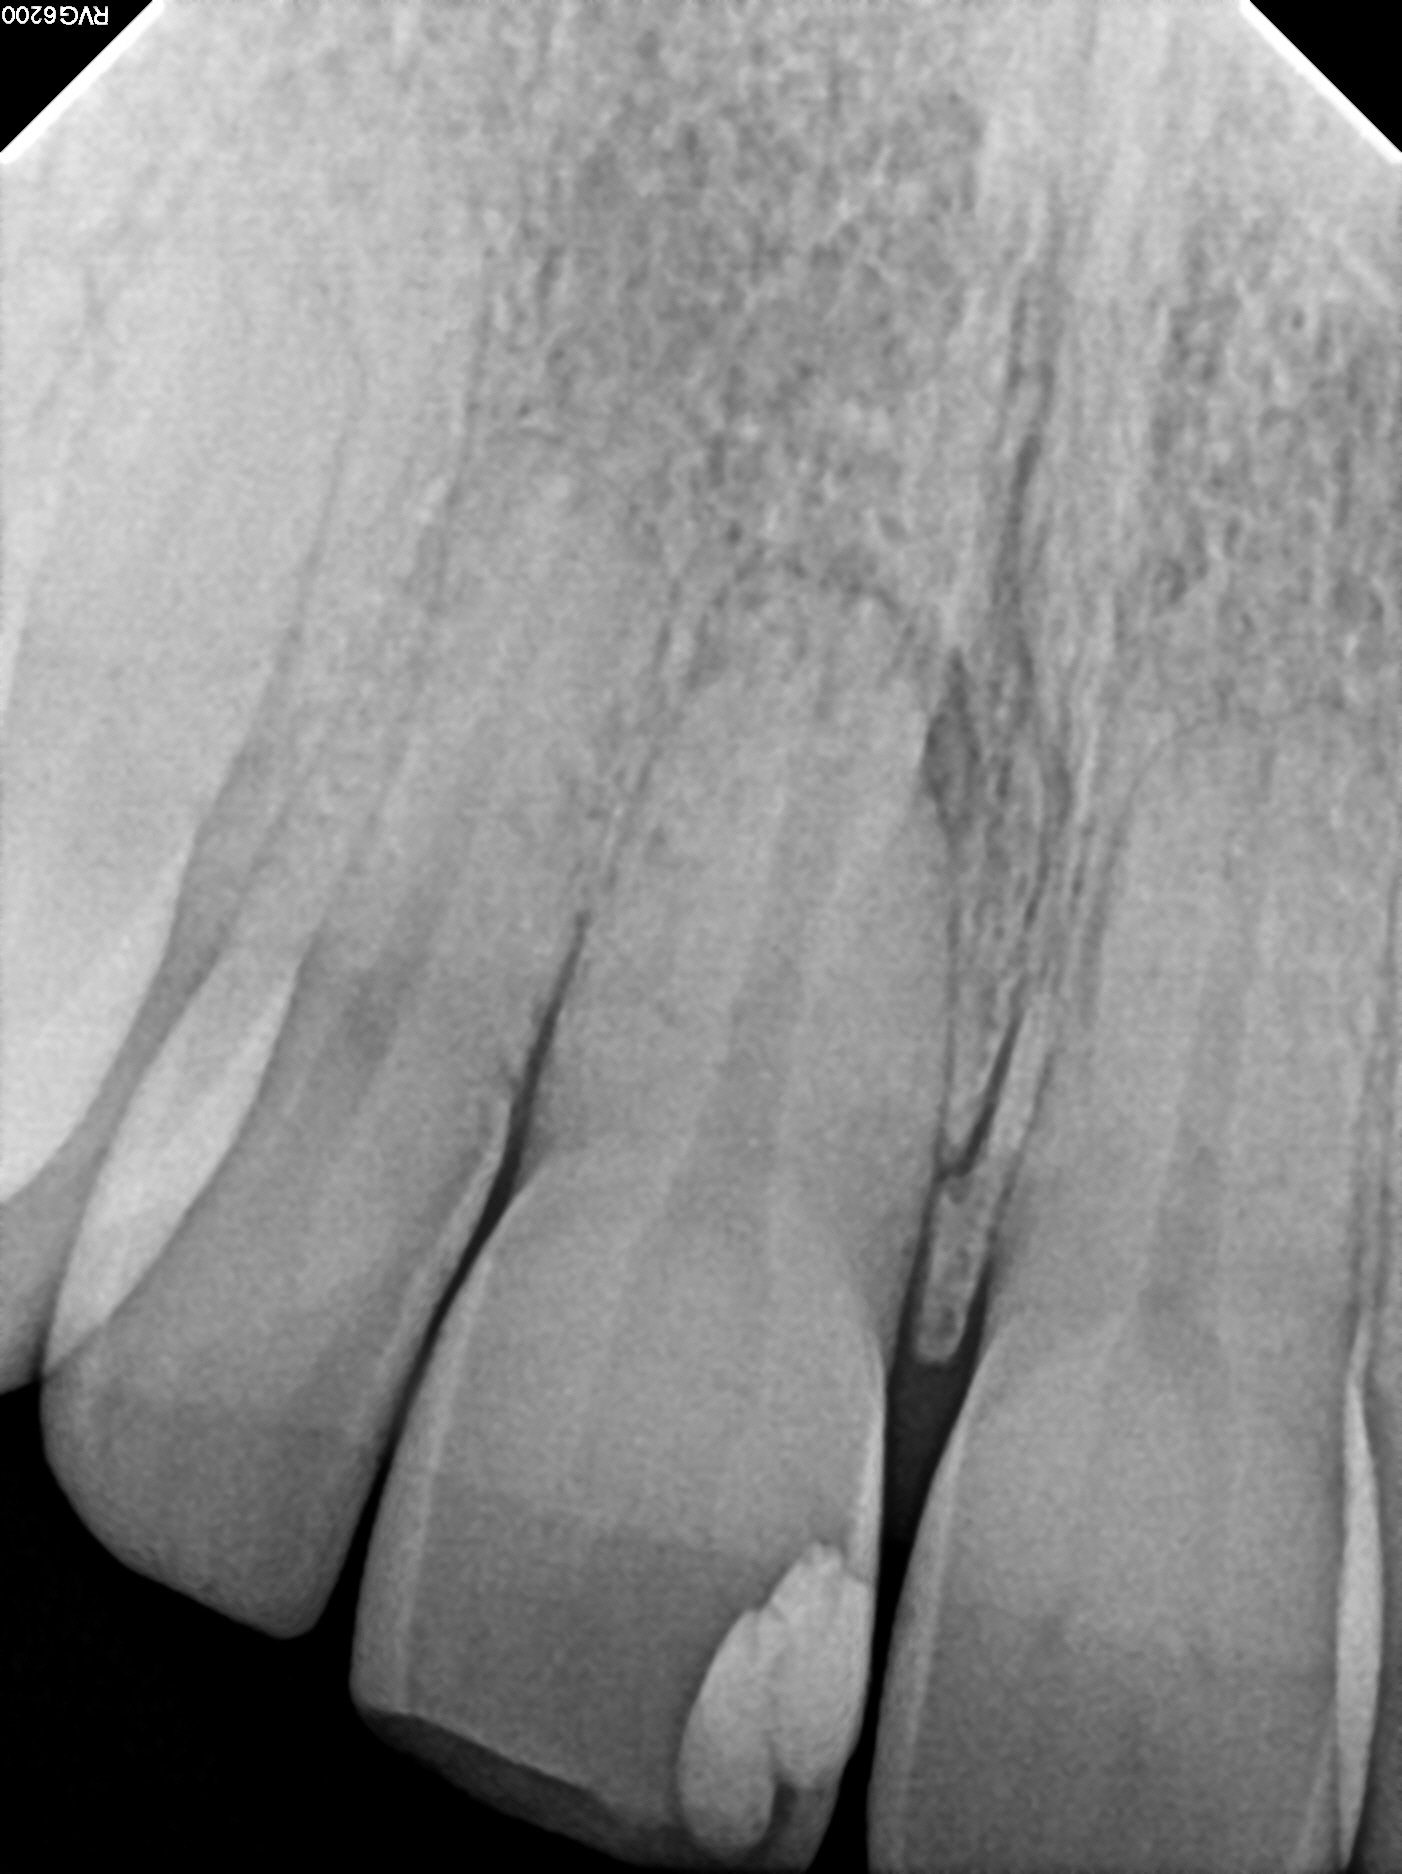

Case 9

This case shows just how curved the roots of teeth can be, which can lead to the nerve canal spaces being difficult to fully treat. These types of cases are often referred to endodontic specialists for treatment due to the added complexity of the curved roots.